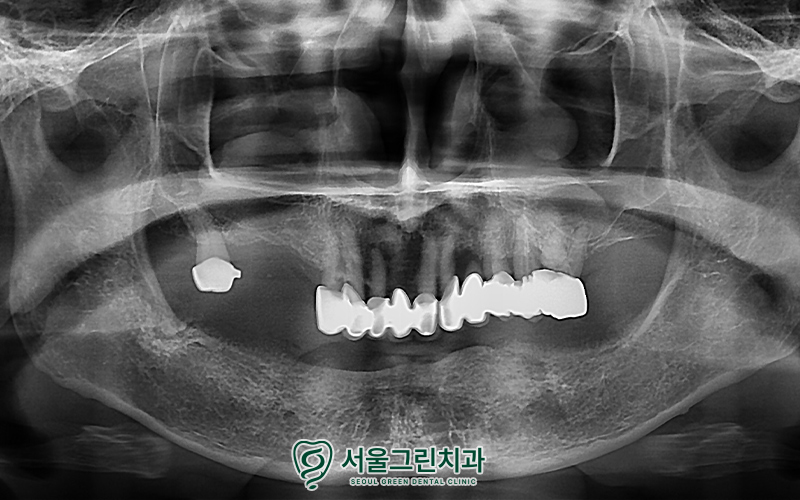

소개해드릴 분은

70대 후반 환자분으로,

아래 틀니의 헐거움과

위쪽 브릿지의 흔들림을 주소로 내원하셨습니다.

.

아래 틀니가 헐거워

음식 섭취 시 불편함을 느끼고 계셨으며,

위쪽 기존 브릿지는 흔들림으로 인해

불안정한 상태였습니다.

엑스레이 사진을 촬영하여

더욱 정밀한 체크를 진행하였고,

환자분과의 충분한 상담을 통해

치료계획을 수립해보았습니다.